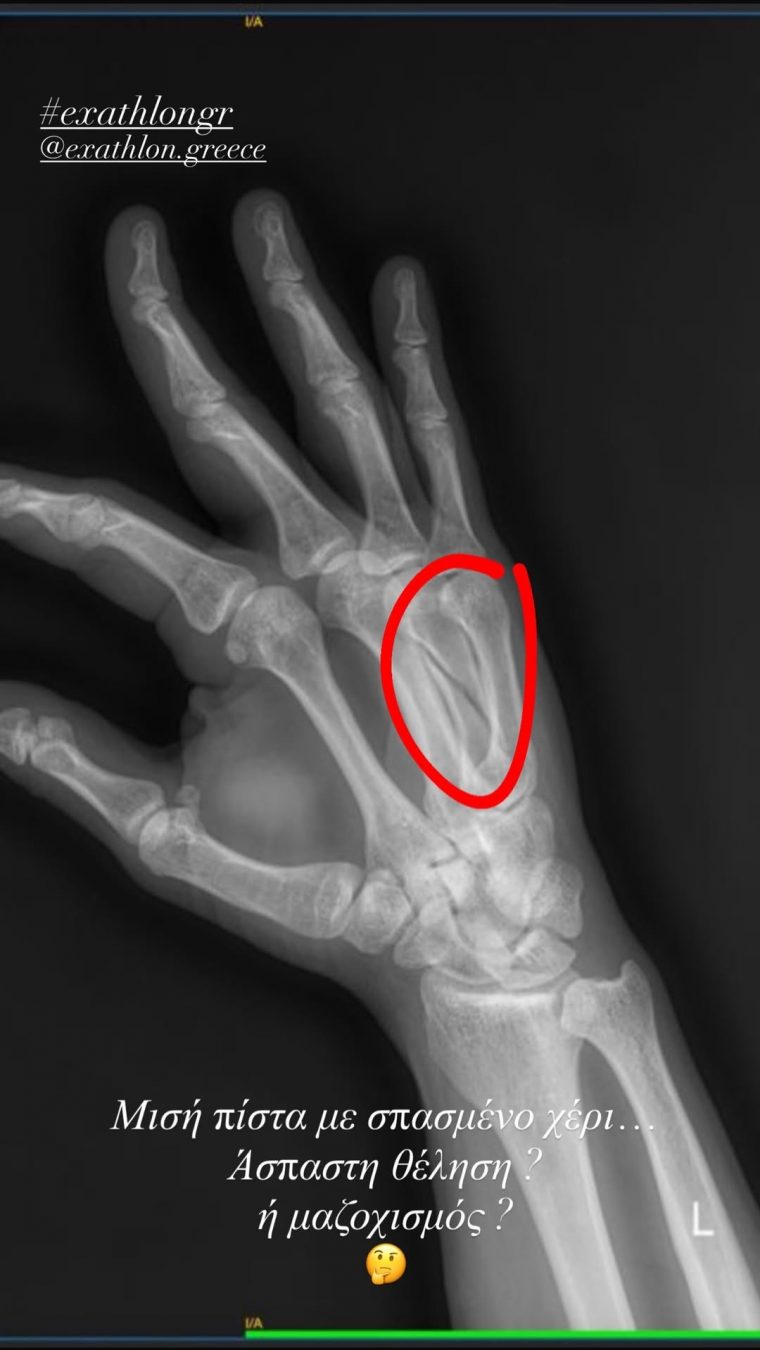

Λίγες ώρες μετά την προβολή του επεισοδίου, ο ίδιος προχώρησε σε μία προσωπική ανάρτηση στον λογαριασμό του στο Instagram, δημοσιεύοντας την ακτινογραφία του σπασμένου του χεριού, όπου φαίνεται καθαρά το κάταγμα.

Στη λεζάντα έγραψε: «Μισή πίστα με σπασμένο χέρι… Άσπαστη θέληση ή μαζοχισμός;»